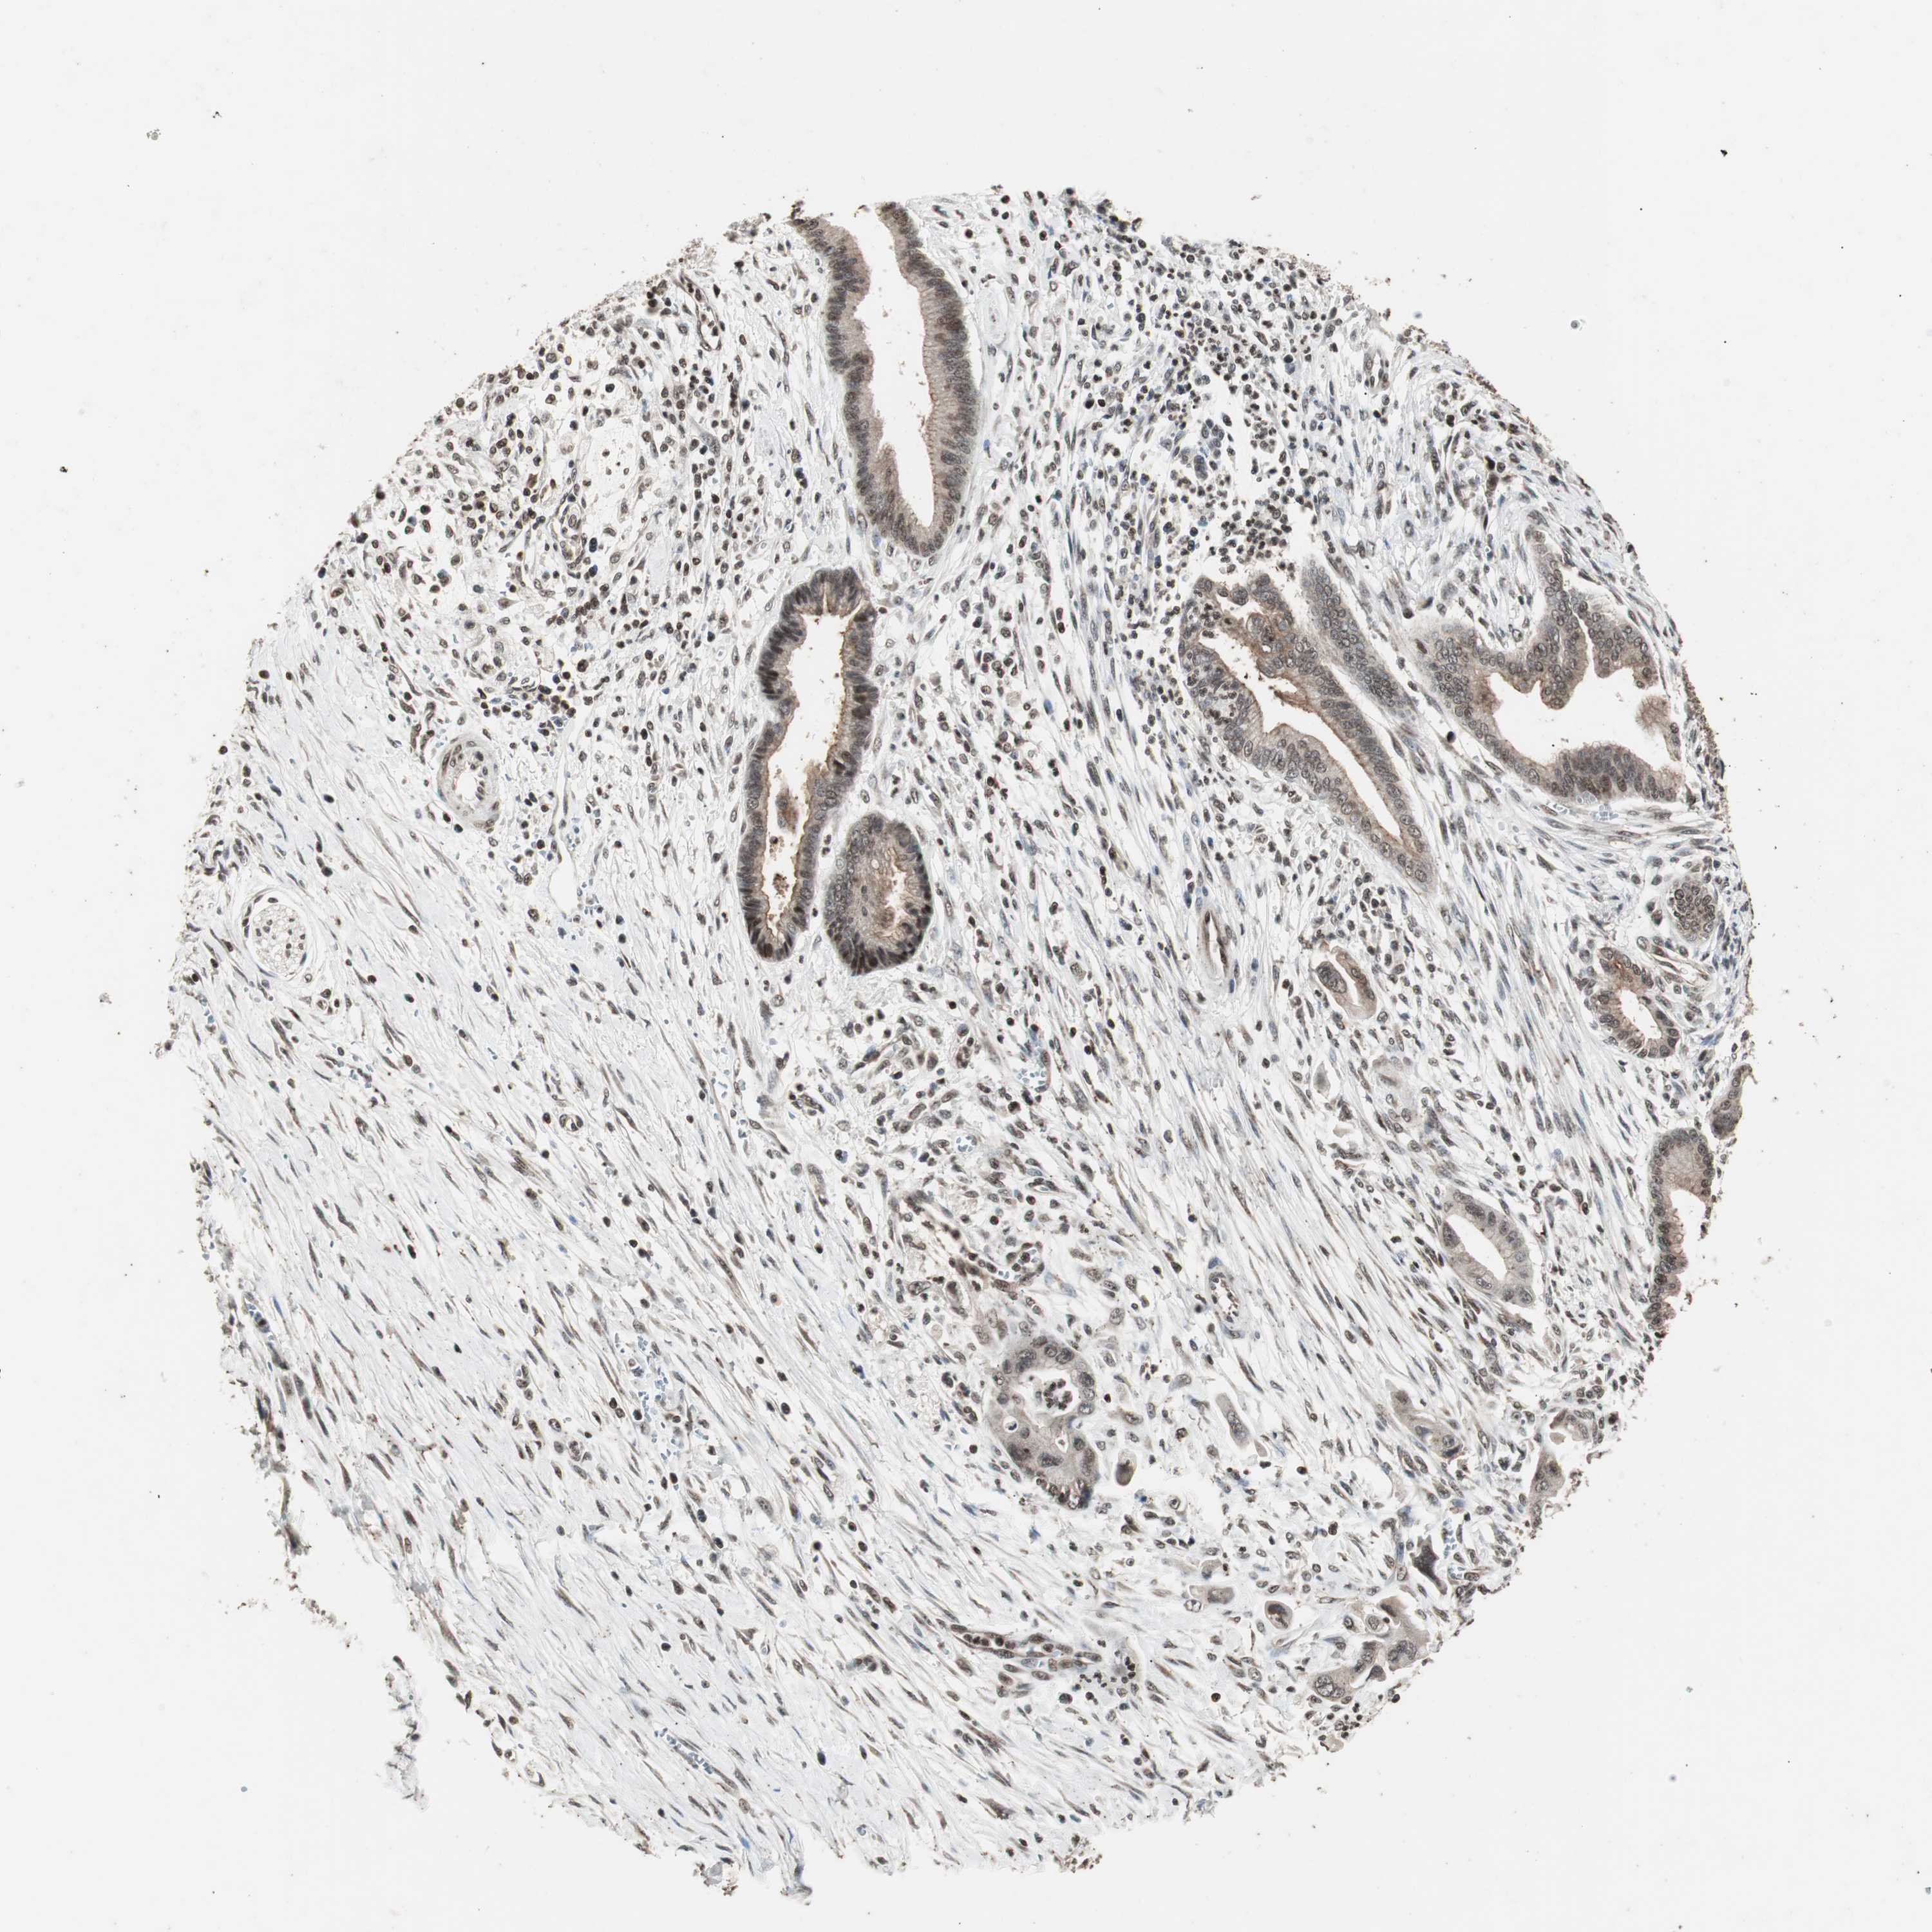

PANCREATIC CANCER - Protein expressioni

A mouse-over function shows sample information and annotation data. Click on an image to view it in a full screen mode. Samples can be filtered based on level of antibody staining by selecting one or several of the following categories: high, medium, low and not detected. The assay and annotation is described here.

Note that samples used for immunohistochemistry by the Human Protein Atlas do not correspond to samples in the TCGA dataset.

Antibody stainingi

Antibody staining in the annotated cell types in the current human tissue is reported as not detected, low, medium, or high, based on conventional immunohistochemistry profiling in selected tissues. This score is based on the combination of the staining intensity and fraction of stained cells.

Each image is clickable and will lead to virtual microscopy that enables deeper exploration of all samples and also displays staining intensity scores, fraction scores and subcellular localization as well as patient and tissue information for each sample.

Antibody HPA007072

Antibody HPA007151

Adenocarcinoma, NOS